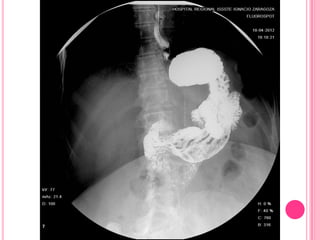

Anillo de Shatzky. SEGD que muestra una indentación de las

paredes anterior y posterior del esófago distal en relación con

anillo de Shatzky, en un paciente con hernia hiatal